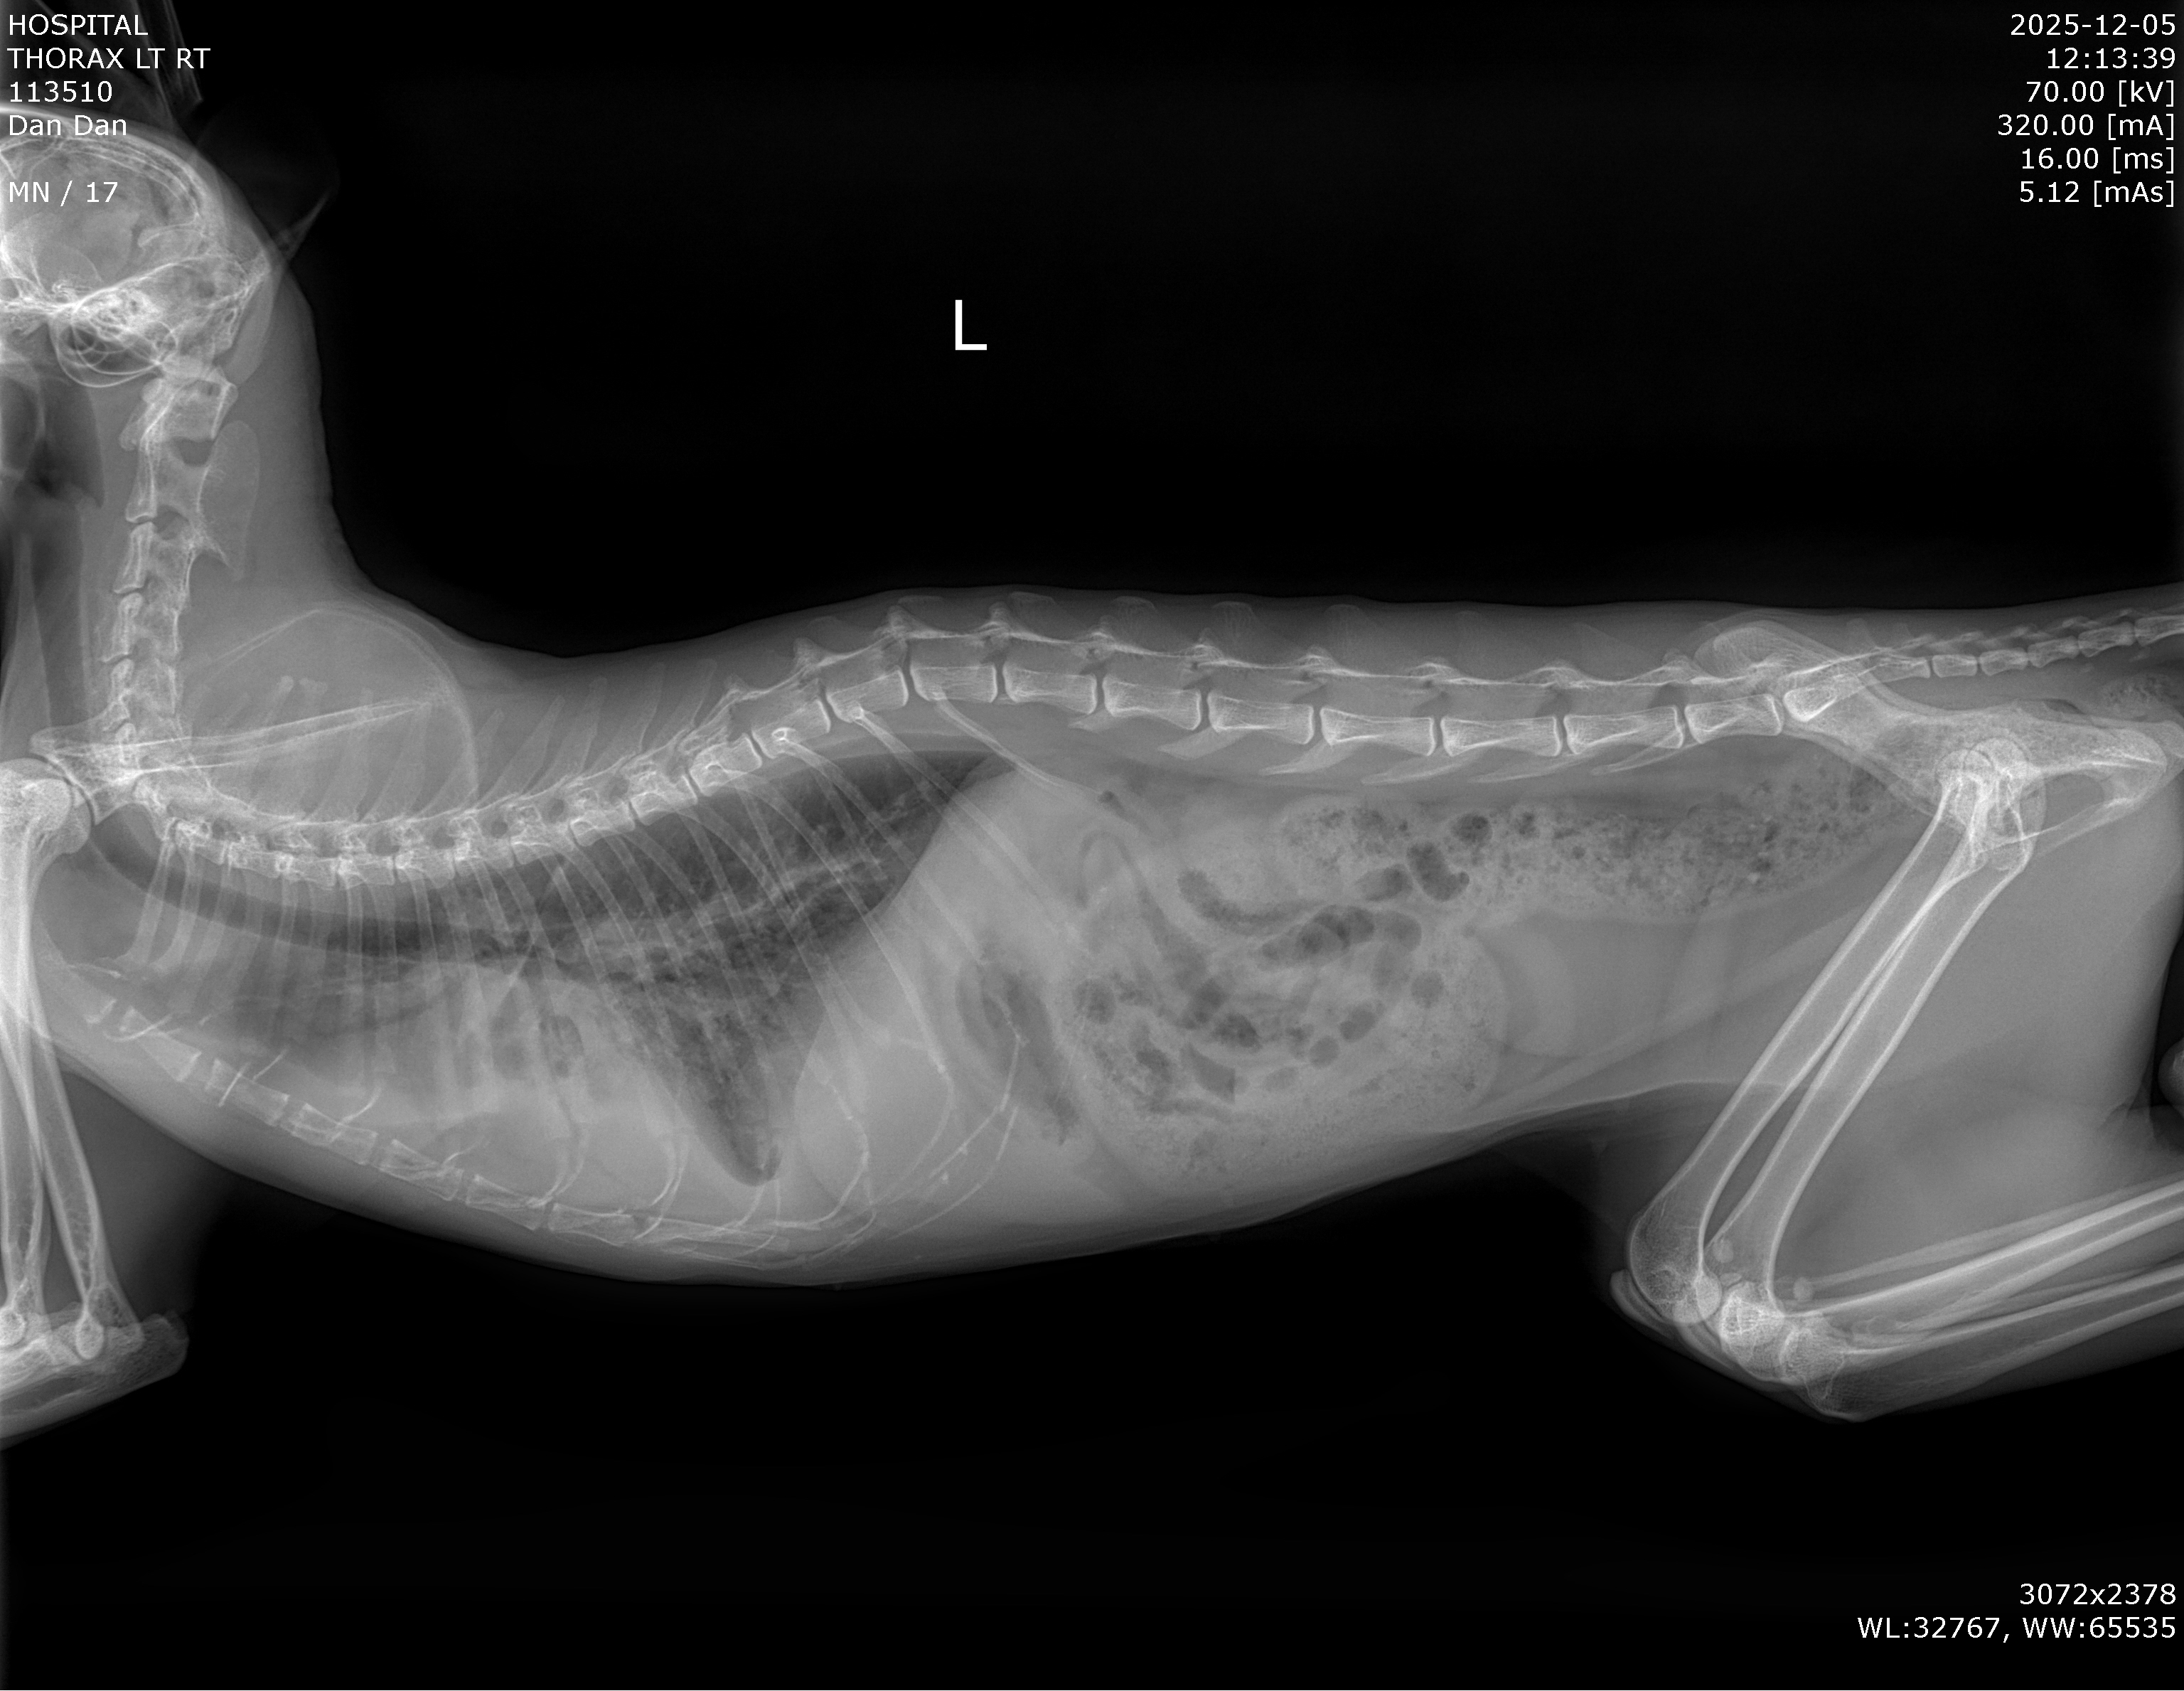

Dan Dan underwent both echocardiography and thoracic radiography.

Findings:

The heart structure had undergone irreversible changes. The heart was overloaded and had entered heart failure.

Dan Dan’s life was at imminent risk.

Dan Dan was in Stage C, already experiencing heart failure.

To relieve the life-threatening pleural effusion, thoracocentesis was performed. Approximately 80 cc of clear fluid was removed.

Dan Dan’s breathing improved immediately — confirming correct diagnostic direction.